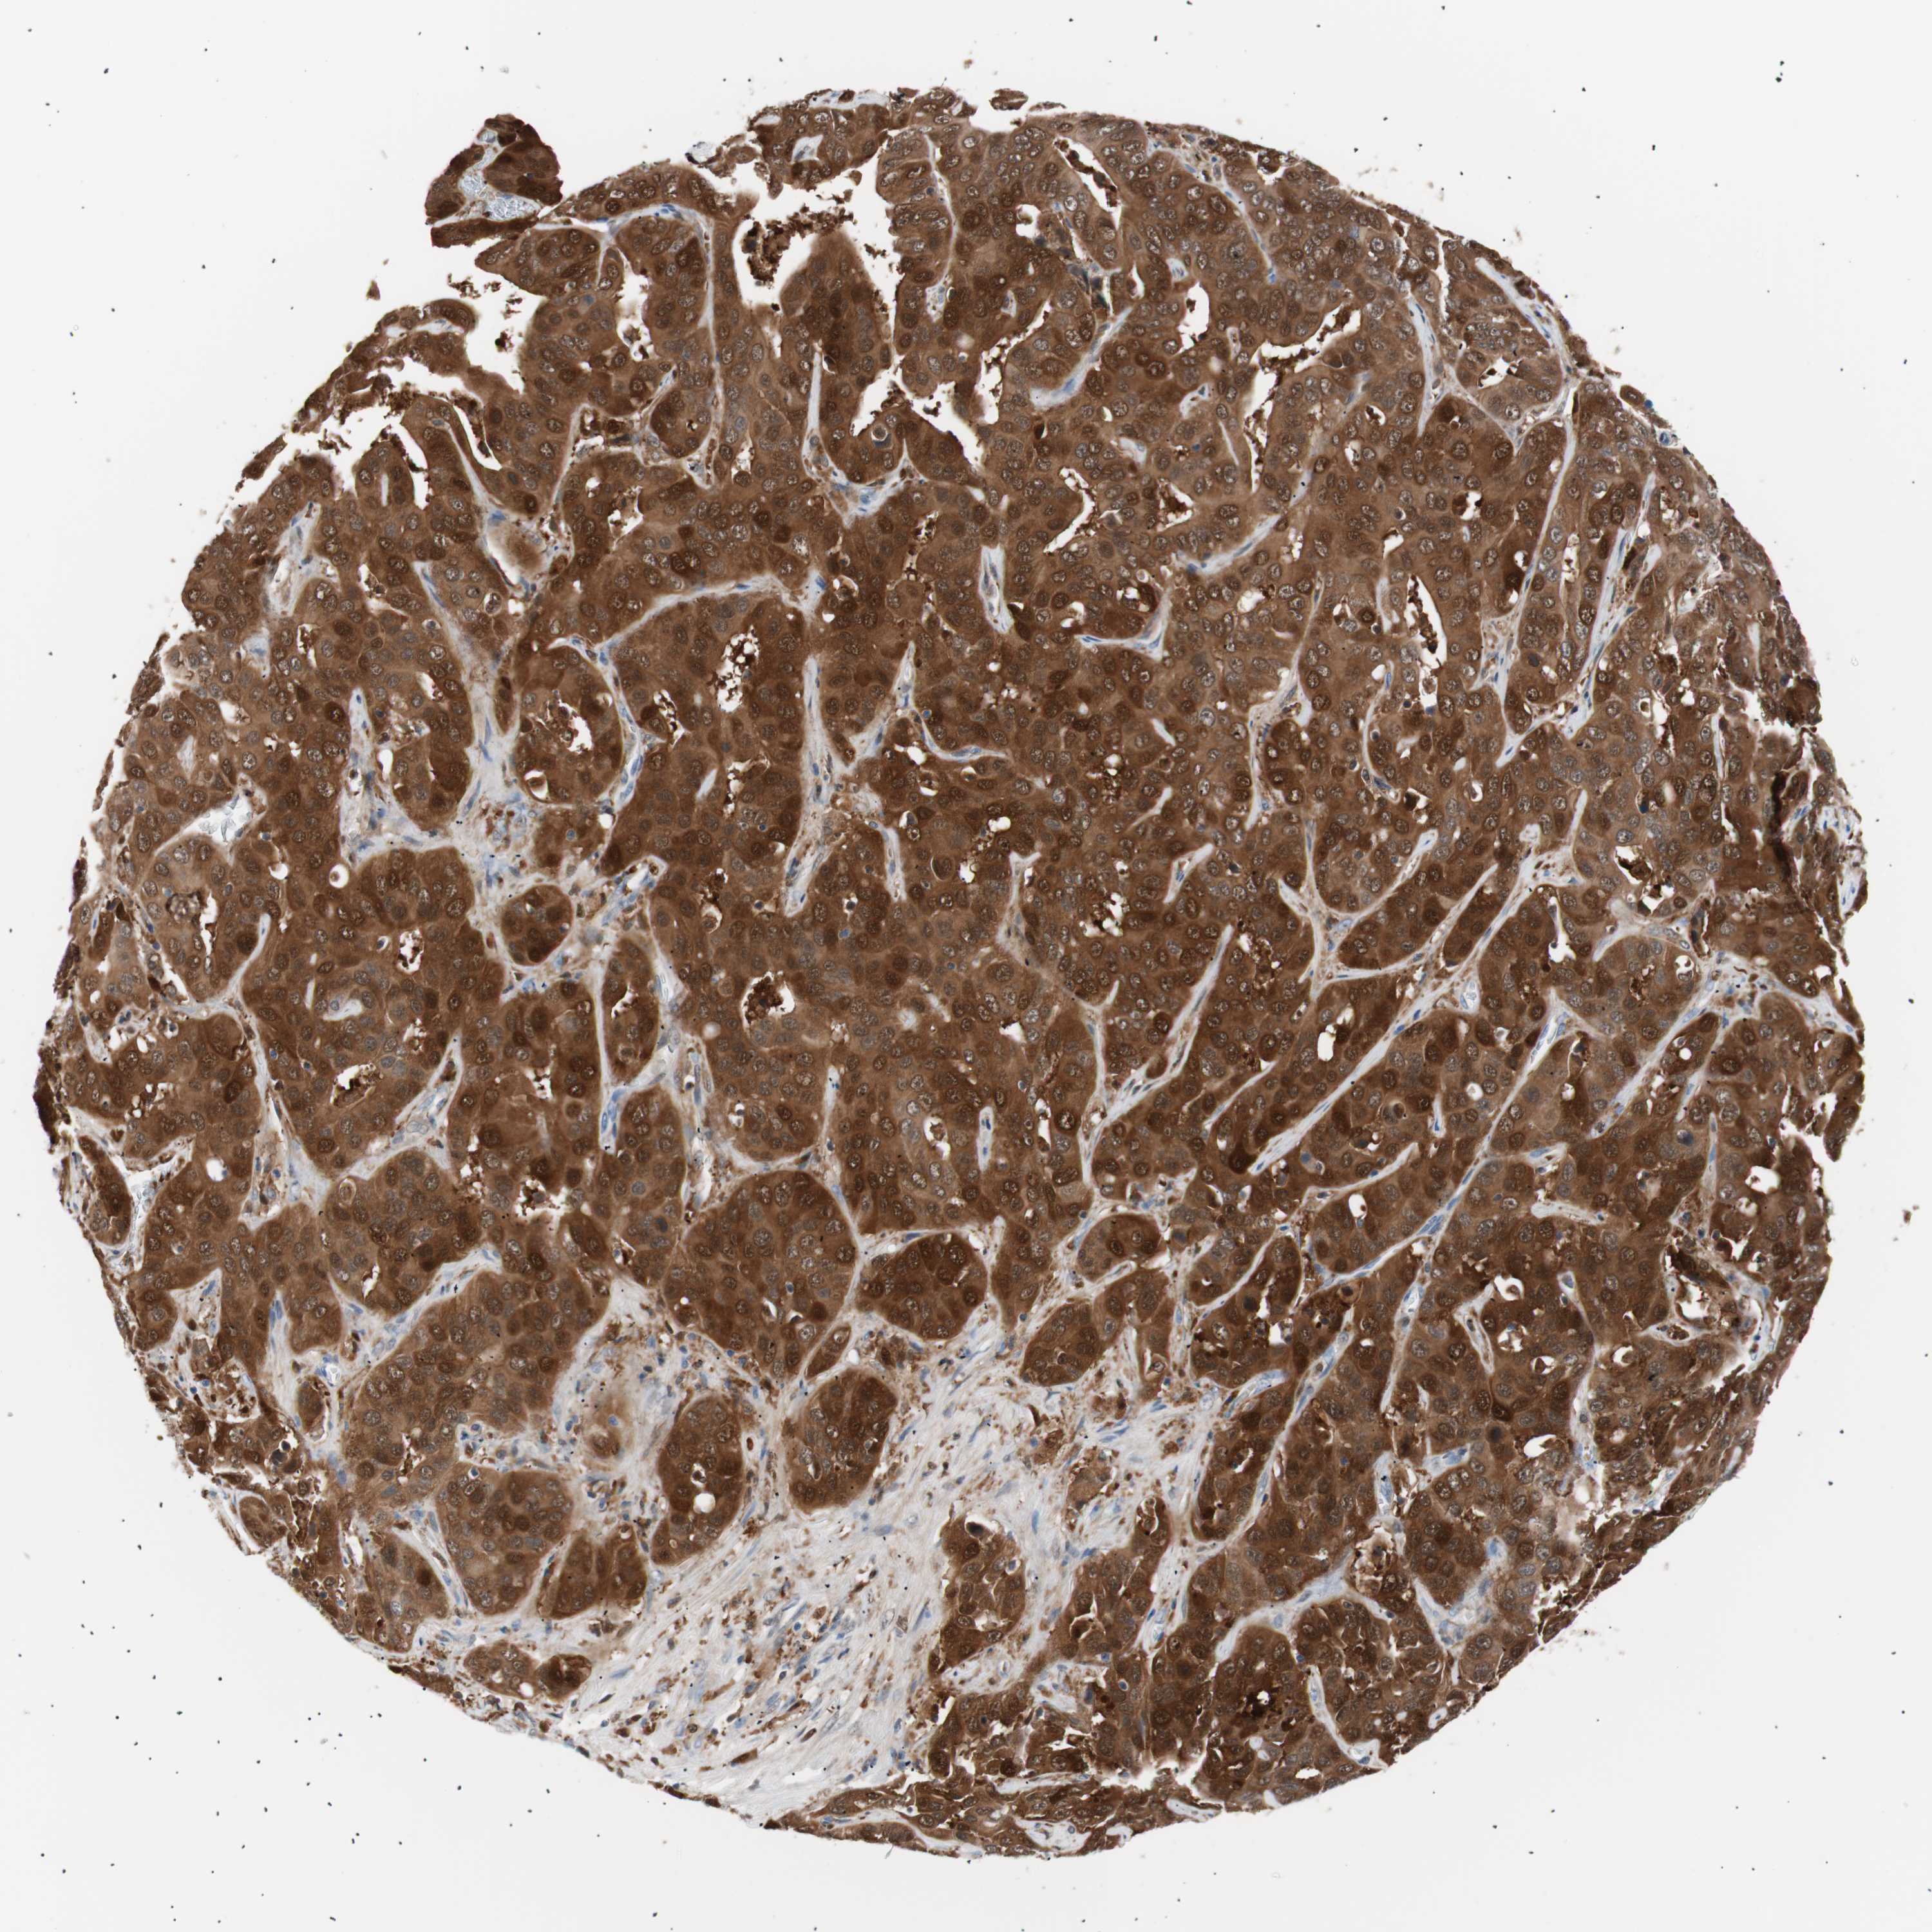

LIVER CANCER - Protein expressioni

A mouse-over function shows sample information and annotation data. Click on an image to view it in a full screen mode. Samples can be filtered based on level of antibody staining by selecting one or several of the following categories: high, medium, low and not detected. The assay and annotation is described here.

Note that samples used for immunohistochemistry by the Human Protein Atlas do not correspond to samples in the TCGA dataset.

Antibody stainingi

Antibody staining in the annotated cell types in the current human tissue is reported as not detected, low, medium, or high, based on conventional immunohistochemistry profiling in selected tissues. This score is based on the combination of the staining intensity and fraction of stained cells.

Each image is clickable and will lead to virtual microscopy that enables deeper exploration of all samples and also displays staining intensity scores, fraction scores and subcellular localization as well as patient and tissue information for each sample.

Antibody HPA003980

Antibody CAB007772

Staining

High

Medium

Low

Not detected

Intensity

Strong

Moderate

Weak

Negative

Quantity

>75%

75%-25%

<25%

None

Location

Nuclear

Cytoplasmic/membranous

Cytoplasmic/membranous,nuclear

Cholangiocarcinoma

Carcinoma, Hepatocellular, NOS